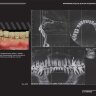

Примеры страниц из книги "Мукогингивальная хирургия вокруг зубов и имплантатов: Работа над ошибками" - А. Ю. Февралёв